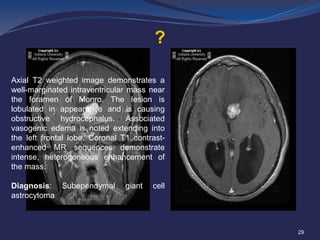

Axial T2 weighted image demonstrates a

well-marginated intraventricular mass near

the foramen of Monro. The lesion is

lobulated in appearance and is causing

obstructive hydrocephalus. Associated

vasogenic edema is noted extending into

the left frontal lobe. Coronal T1 contrastenhanced MR sequences demonstrate

intense, heterogeneous enhancement of

the mass.

Diagnosis: Subependymal

astrocytoma

giant

cell